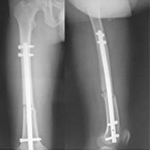

張某,男,50歲,因“左股骨骨不連”入院。植骨+PRP治療后8月完全愈合。

術后完全愈合